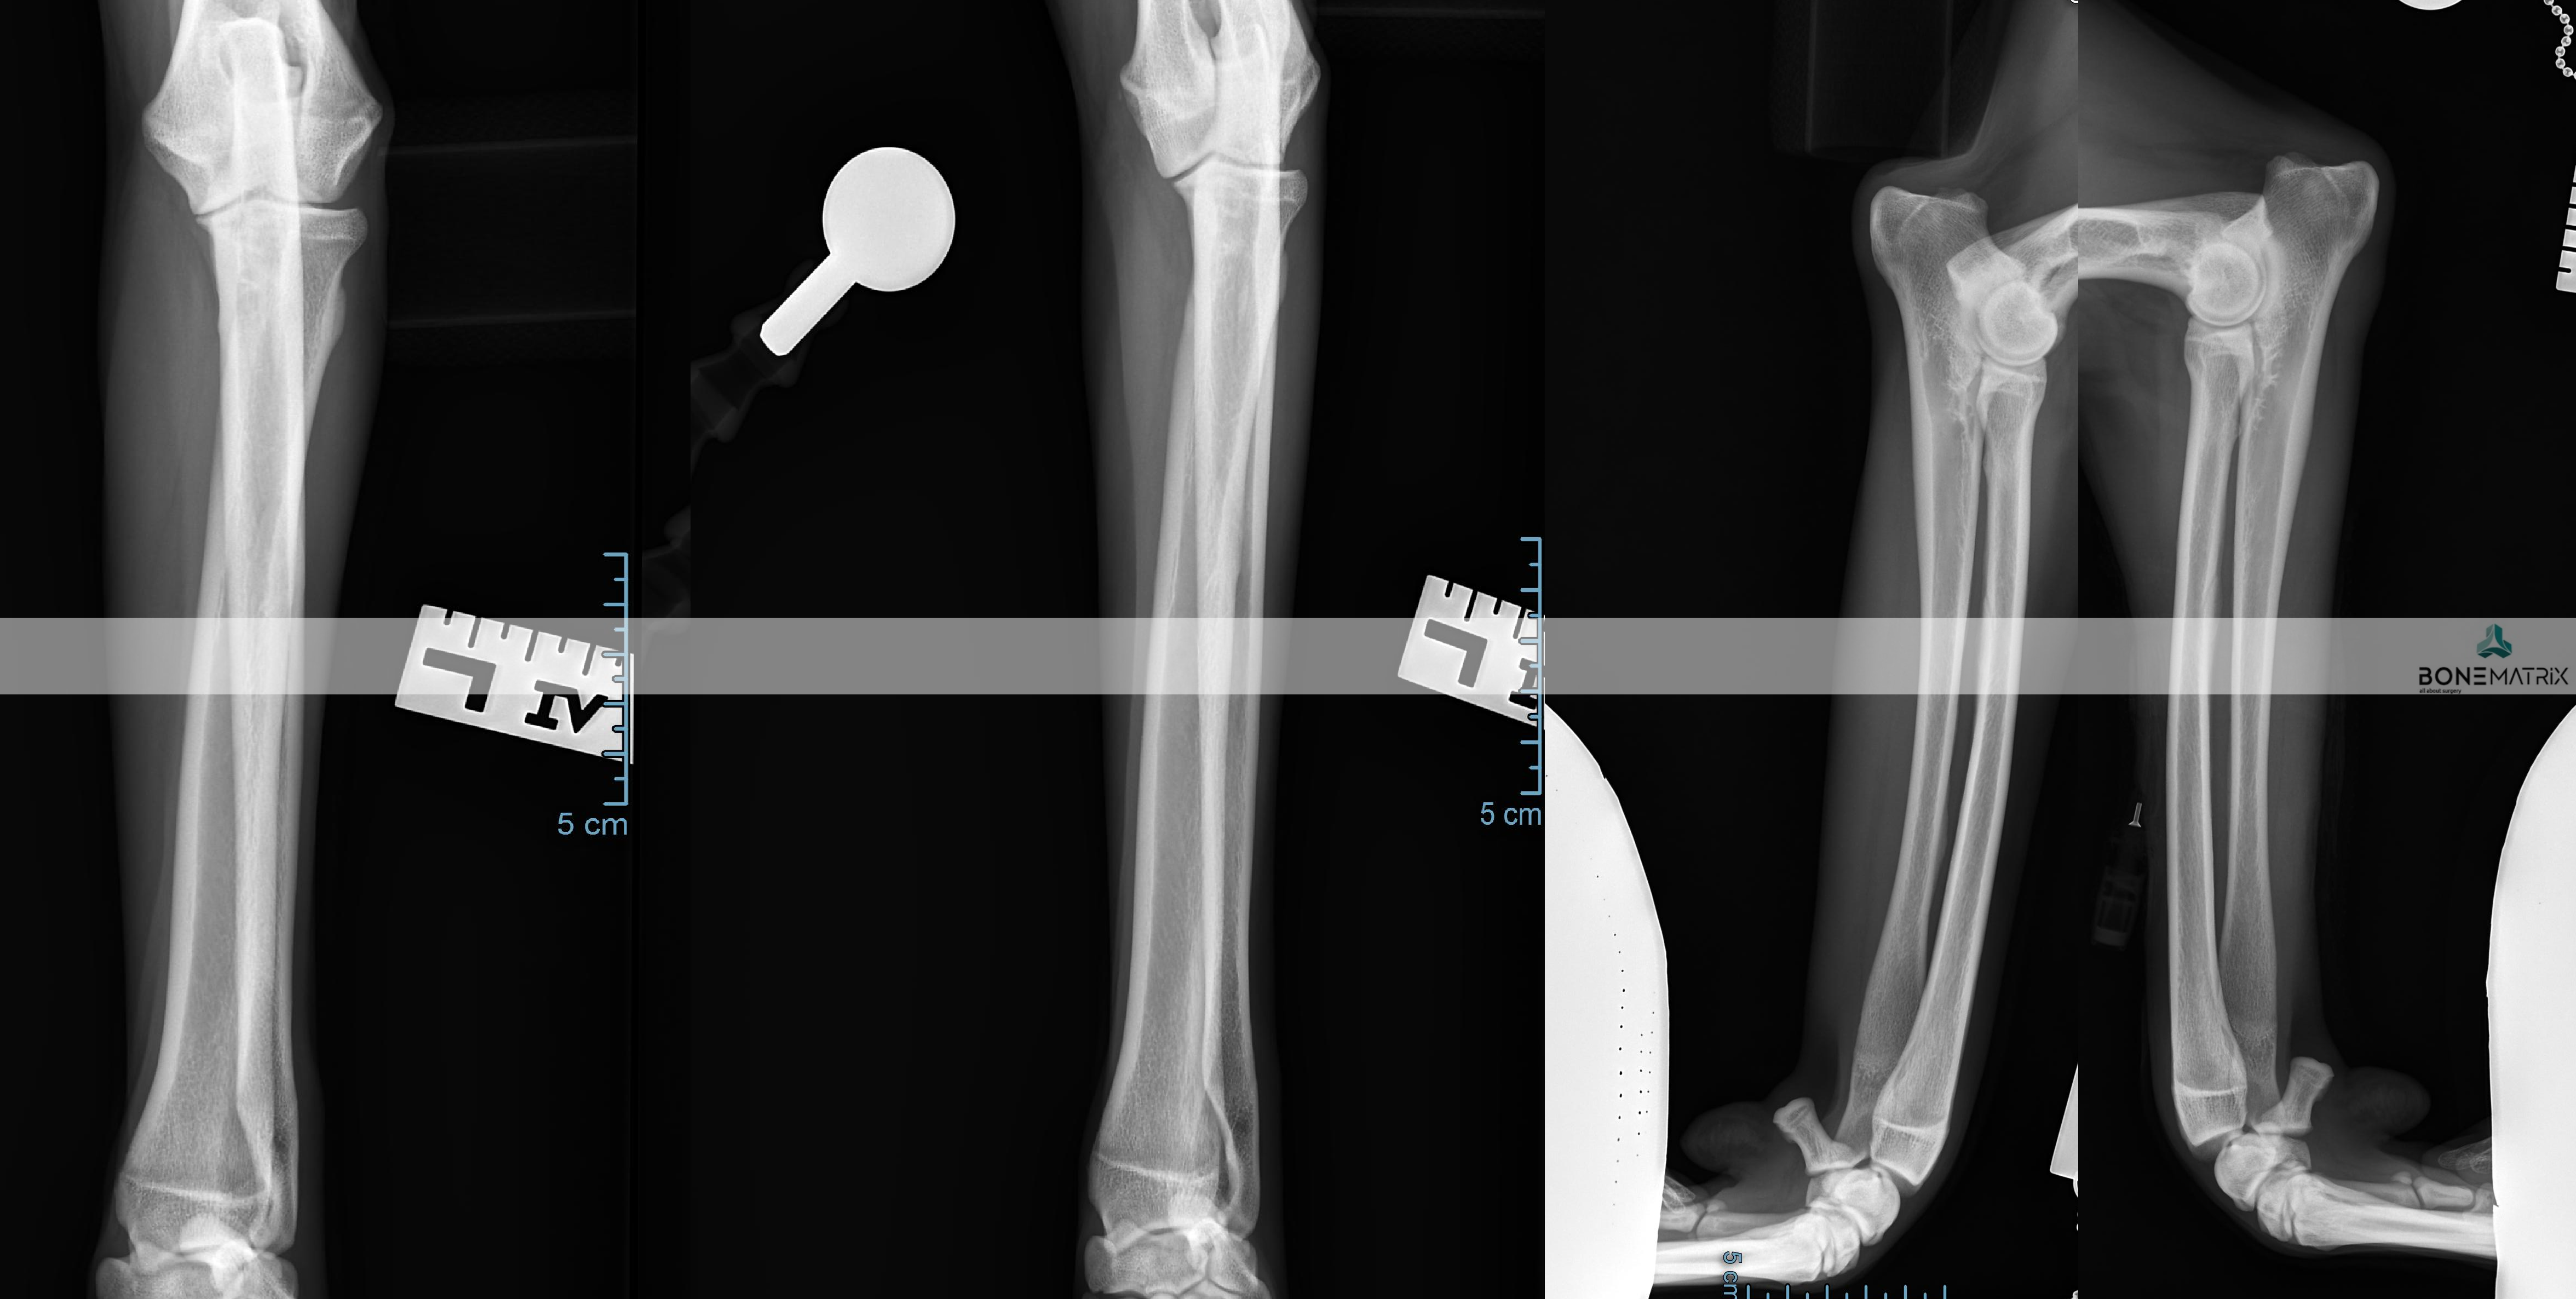

O que é?

As deformidades angulares são patologia que podem assumir as mais variadas apresentações.

A sua origem pode estar relacionada com fatores genéticos, traumas sofridos durante a imaturidade do animal, pode apresentar-se como uma doença de desenvolvimento e pode também ter influências ambientais ou nutricionais.

Todas elas se caracterizam-se por um desvio na correta forma de um determinado osso ou membro.

Que consequências podem surgir da apresentação de uma deformidade angular?

As consequências da apresentação de deformidades angulares estão em muito relacionadas com a localização destas e com a exuberância da apresentação.

Estes desvios da conformação normal podem provocar desde osteoartrite articular ou laxitude dos mecanismos de estabilização de articulações até incapacidade na realização da marcha do animal afetando severamente a qualidade de vida deste.

O diagnóstico é realizado por meio de análise clinica da anatomia dos membros e é estudada por norma através da realização de um estudo radiográfico.

O animal poderá ser desde assintomático a apresentar sintomas que passam por claudicação, lesões em estruturas articulares consequentes destes desvios angulares, incapacidade na realização de determinados movimentos até incapacidades severas de mobilidade.

A realização de um estudo radiográfico é imprescindível para definição de um planeamento cirúrgico de correção.

Em casos mais complexos pode ser necessário o recurso a estudos de imagem avançada, tanto para o estudo da deformidade como para a produção de instrumentos de cirurgia (guias de corte 3D, produção de placas com customizadas) para que seja realizada a cirurgia com precisão.

Qual o tratamento indicado?

O tratamento depende sempre da forma da patologia apresentada.

Por norma envolve realização de cortes ósseos, definidos com determinada angulação para que seja corrigida a deformidade angular, com subsequente estabilização da fratura induzida com a utilização de placas e parafusos bloqueados (sistema que oferece a maior segurança para a estabilização de fraturas).

PTO (proximal tibial osteotomy) é um procedimento cirúrgico utilizado para correção de deformidades angulares presentes na tíbia.

A realização deste procedimento exige um estudo radiográfico com planeamento cirúrgico anterior ao procedimento cirúrgico. Neste são medidos ângulos relacionados com o alinhamento do membro posterior.

A cirurgia consiste na realização de dois cortes, previamente planeados, na tíbia, seguindo-se a sua estabilização por meio de placa e parafusos bloqueados (estes implantes apresentam um alto grau de segurança na sua utilização).

Dada a versatilidade desta técnica, várias patologias podem ser corrigidas com esta abordagem, nomeadamente luxações de patela e outras deformidades do membro posterior.

Nesta cirurgia também são utilizadas com frequência guias 3D que definem o local de corte com elevada precisão. Estas guias são planeadas a partir de imagem de TAC em softwares de especialidade e seguidamente são produzidas no nosso laboratório 3D, de forma a estarem adaptadas as características individuais de cada paciente.